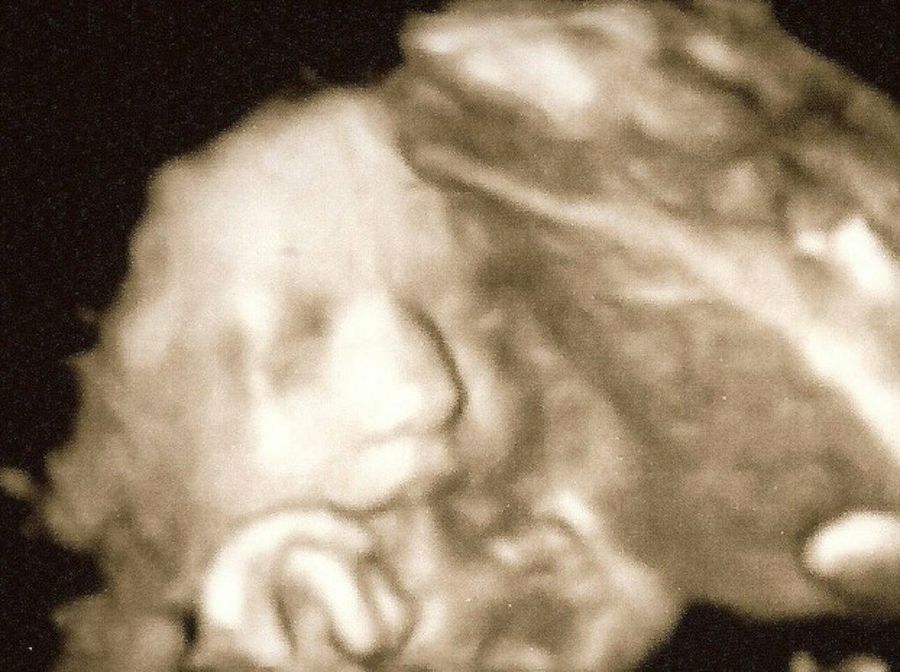

ecografia feto

Es importante tener controlada la tensión de la mujer embarazada durante las últimas semanas de embarazo. Los nervios o el simple estado en que nos encontramos hace que podamos tener subidas que puedan perjudicar un riesgo para el embarazo. Además, es bueno controlar los movimientos fetales. El bebé se va a mover menos, está completamente formado y tiene un espacio reducido para hacerlo. Cuando esté colocado para el momento del parto no notarás apenas su movimiento.